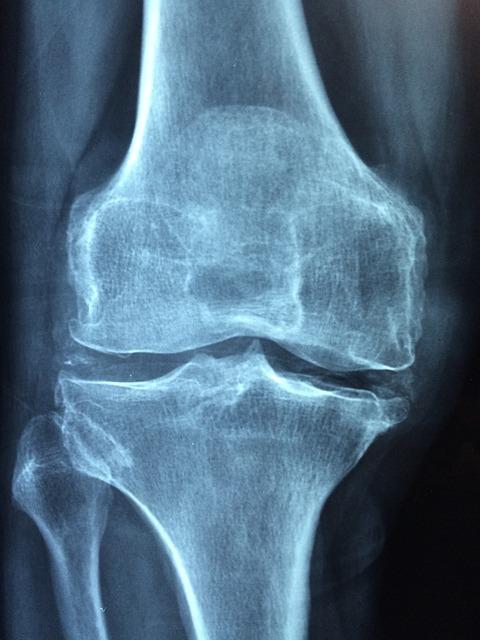

Osteoarthritis: This is the most common form of arthritis, caused by the breakdown of cartilage, the protective cushion between bones. This breakdown leads to bone rubbing against bone, causing pain, stiffness, and reduced range of motion. Risk factors include age, genetics, obesity, and previous joint injuries.

Rheumatoid Arthritis: This is an autoimmune disease where the body’s immune system mistakenly attacks the lining of the joints. This causes inflammation, pain, swelling, and stiffness. Rheumatoid arthritis can affect multiple joints together and can lead to joint damage over time.